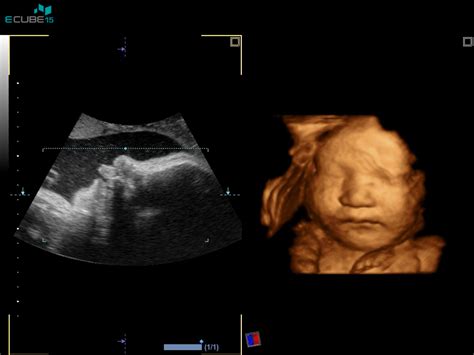

1. Nuhalna svetlina (prvo trimesesečje):Nuhalna svetlina je ultrazvočni presejalni test, ki se običajno opravi med 11. in 14. tednom nosečnosti. Njegov namen je oceniti tveganje za kromosomske nepravilnosti, kot je Downov sindrom. Pri nosečnicah z dvojčki je ta pregled še posebej pomemben, saj se tveganja lahko razlikujejo.

- Prim. mag. Uršula Reš Muravec, dr. med., Maja Merkun, dr.: Nuhalna svetlina je 35 €. Dodatno ponujajo Morfologijo ploda (20.-24. teden) za 100 €, NIPT teste (NIFTY basic 350 €, standard, dvojčki 390 €, plus 590 €, pro 890 €), merjenje dolžine materničnega vratu (23. teden) za 40 €, kontrolo rasti (30. teden) za 70 €, bris za streptokok agalakcije (35.-37. teden) za 75 € in 3D/4D ultrazvok (25.-30. teden) za 110 €.

- mag. Mili Lomšek, dr. med., Irena Tonin, dr.: Cena nuhalne svetline je 90 €. Dodatne storitve vključujejo zapis na USB za 15 €. Ponujajo Dvojni hormonski test za 50 €, Četverni hormonski test za 65 €, Potrditev nosečnosti za 50 €, Morfologijo ploda (20.-22. teden) za 100 € (120 € za dvojčke), NIPT teste (NIFTY basic 350 €, standard, dvojčki 390 €, plus 590 €, pro 890 €), merjenje dolžine materničnega vratu za 45 €, kontrolo rasti in lege ploda za 70 € (80 € za dvojčke), CTG v nosečnosti za 50 € ter 3D/4D ultrazvok (+USB) za 120 €.

- 3D/4D ultrazvok: Omogoča podrobnejši vpogled v izgled in vedenje plodov. Cene se gibljejo od 80 € do 120 €.